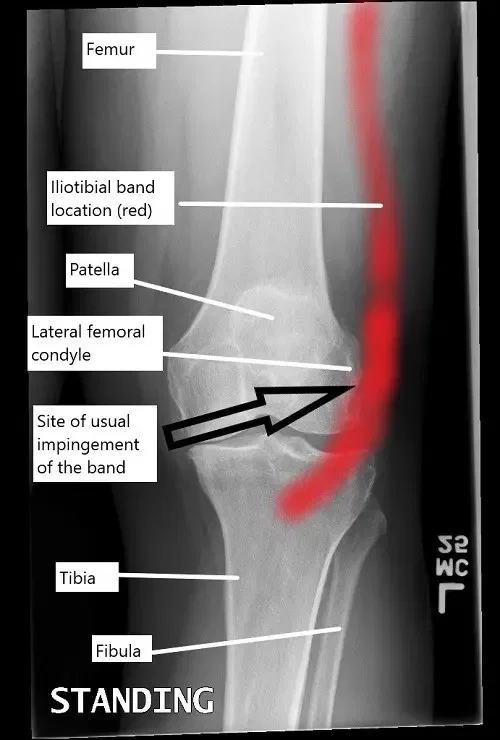

A knee x-ray illustrating the location of iliotibial band and the usual site of impingement.

The iliotibial band is a fibrous band that runs along the outer side of the thigh, extending from the hip to the shinbone. It connects the tensor fascia lata and gluteus maximus muscles to the tibia. The ITB helps stabilize the knee during activities such as walking, running, and cycling. Normally, the ITB moves smoothly over the lateral femoral condyle as the knee bends and straightens. However, when the ITB becomes tight or irritated, it can rub against the femoral condyle, leading to inflammation and pain.